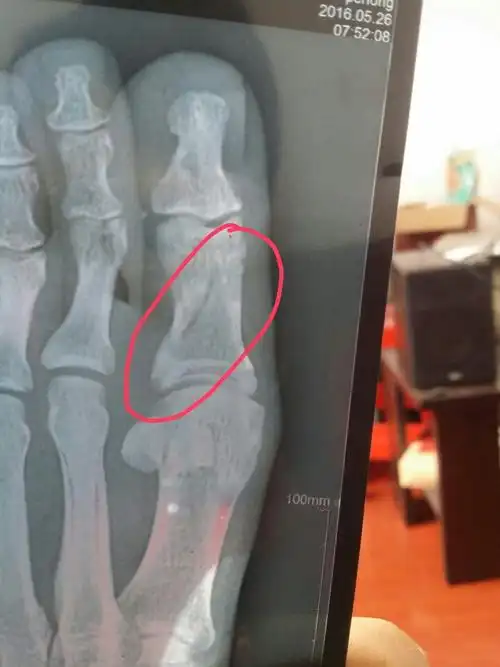

这个属于骨裂还是骨折,不打石膏可以吗